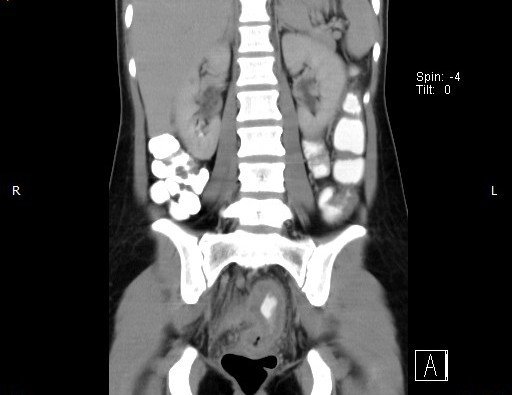

Abdominal CT images

CT finding : Circumferential rectal wall thickening-> Tissue diagnosis -> Rectal cancer

CT finding correlated with plain abdominal radiograph